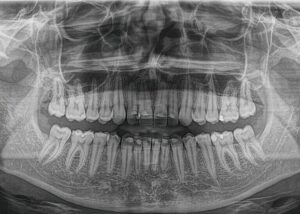

Fotografimi i dhëmbeve- Ortopani

- Rëntgeni Ortopan, mundëson identifikimin mjaftë të suksesshëm të dhëmbëve, të nofullës së poshtme dhe të sipërme, si dhe formacionet patologjike të kockave të nofullës.

- Karakteristika më e rëndësishme është zbulimi i të gjitha detajeve që janë të pamundur të vërehen përmes shikimit me sy si dhe kontribojnë në diagnostikimin dhe trajtimin e saktë nga mjeku.

- Për këtë arsye pas ekzaminimit të parë të pacinetit sipas kërkesave shërben si një prej metodave më të kërkuar në drejtim të përcaktimit të trajtimit.